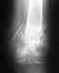

Zdravstvuyte..ya pisal vam v4era po povodu travmi, vy skazali 4to neobhodima rentgenogramma, ya proskaniroval snimok polutoramesya4noy davnosti, posledniy snimok k sojaleniyu ne polu4ilos' proskanirovat', mozol na vneshney lodyzhke uje yest' i otnositelno horoshaya, na vnutrenney perelom zajil hotya boli yest' yesli mnogo hoju s kostylem...$to bespokoit tak eto strah- a budu li ya hodit' ne hromaya, mneniya zdes' razdelilis', nekotorye govoryat operatsiya nujna...snimok otpravlyayune budu mnogo pisat' vy i ak vsyo uvidite...